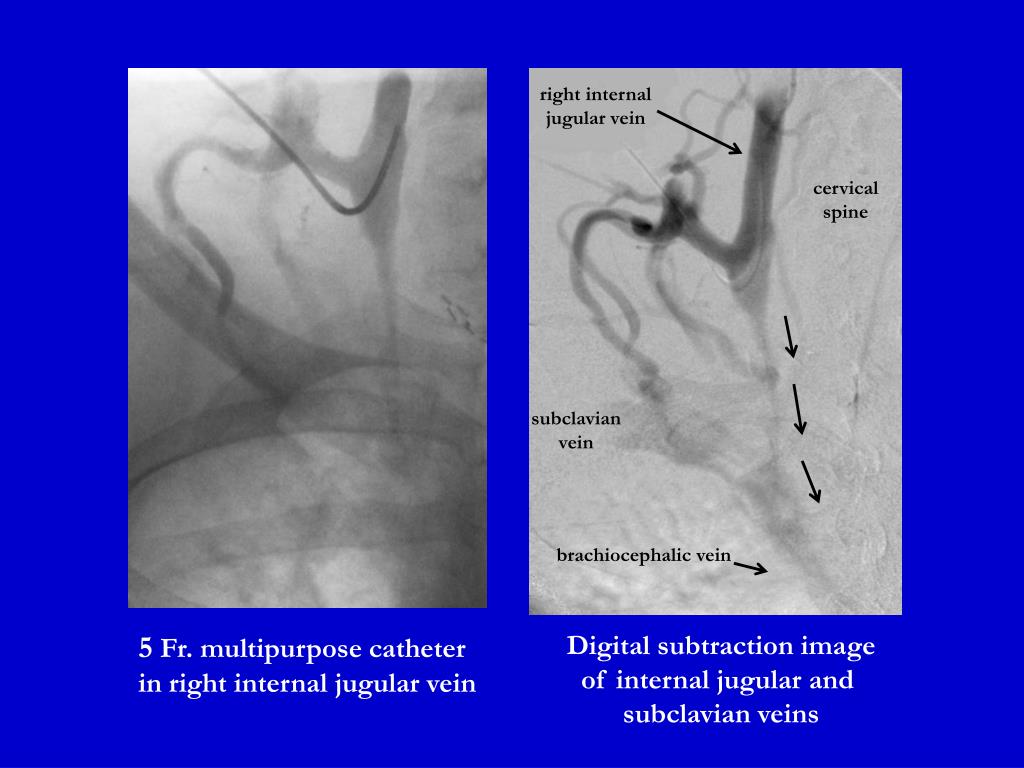

PPT 5 Fr. multipurpose catheter in right internal jugular vein Right Internal Jugular Vein Catheter Cpt Subclavian, internal jugular or femoral). A central venous access device/catheter is a device whose tip must terminate in the brachiocephalic. for ultrasound and fluoroscopic guided placement of a tunneled hemodialysis catheter placement through the right internal. Central venous catheter (cvc) is a cannula placed in a central vein (e.g. the internal jugular vein on the right is larger. Right Internal Jugular Vein Catheter Cpt.

PPT 5 Fr. multipurpose catheter in right internal jugular vein Right Internal Jugular Vein Catheter Cpt A central venous access device/catheter is a device whose tip must terminate in the brachiocephalic. Central venous catheter (cvc) is a cannula placed in a central vein (e.g. for ultrasound and fluoroscopic guided placement of a tunneled hemodialysis catheter placement through the right internal. a central venous catheter (cvc) is an indwelling device inserted into a large, central. Right Internal Jugular Vein Catheter Cpt.